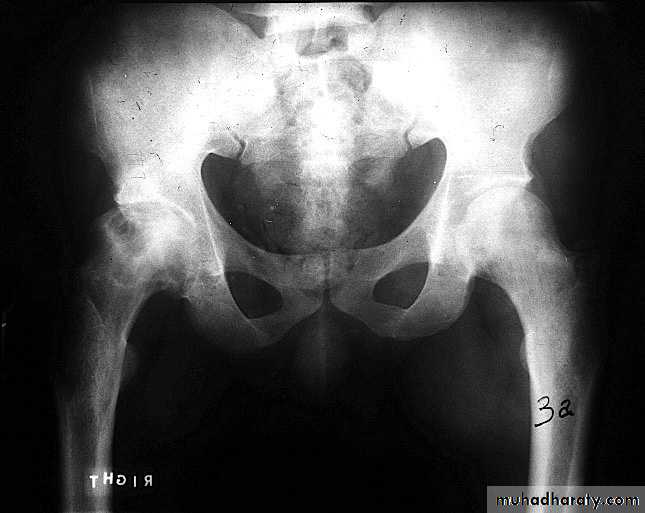

.bone deformity vertebral bodies are biconcave , the femora may be bowed & in severe cases the side walls of the pelvis may bend inwards , giving to the so called triradiate pelvis .

Hyperparathyroidism:

Excess parathyroid hormone secretion mobilizes calcium from the bones , resulting in a decrease in bone density , it may be primary from hyperplasia or tumour of the parathyroid glands or secondary to chronic renal failure. generalized loss of bone density.